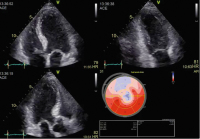

Echo

Abbildung 8: Apikaler 4-, 2- und 3-Kammerblick und zugehörige Bull’s-Eye-Darstellung des linksventrikulären longitudinalen Strains: Es zeigt sich eine deutliche Einschränkung der Kontraktilität im Bereich des Apex, des Septums, der anteroseptalen Wand sowie der Vorderwand (LAD-Versorgungsgebiet) bei STEMI der Vorderwand.

Keywords: Bull's-Eye-ViewEchoKardiologieSTEMI